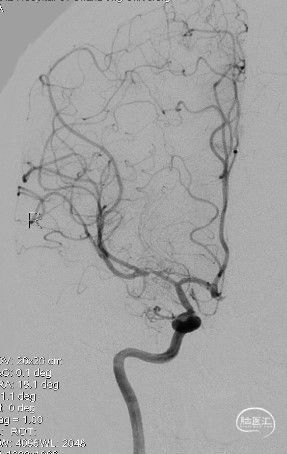

造影:右侧颈内动脉末端变细,大脑前及大脑中自起始部闭塞,脑底少量烟雾血管形成,汇聚使R-MCA少量分支显影。

右侧颈内动脉正位:

右侧颈内动脉侧位:

造影:右侧颈内动脉末段变细,右侧大脑中动脉M1段分叉前重度狭窄,豆纹动脉增多,右侧大脑前动脉向大脑中动脉分布区代偿供血:

三维重建显示右侧大脑中动脉分叉前部重度狭窄,狭窄段直径0.4mm,狭窄程度约84%: